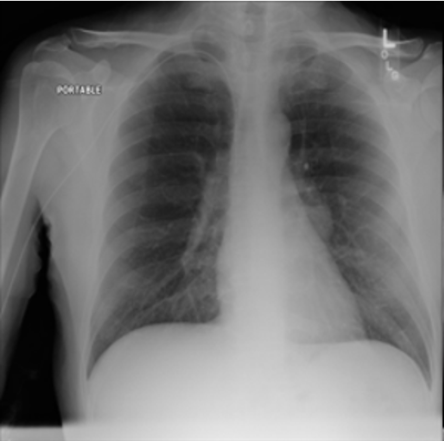

4.1 Qualitative Evaluation of Healthy Counterpart Generation

Example images from the disease COVID-19 Radiography Database and their generative healthy counterparts are given in figure 2. The images on the far left are instances of the lung opacity class from the real images in the dataset. The images in the middle column are examples of the generated healthy counterfactuals obtained via latent space diffusion, with RadBERT-guided textual-conditioning via a conditional prompt “normal chest x-ray”. A total of 75 diffusion inference steps are used with image conditioning strength=0.85 and guidance scale=7.5. (The former indicates the level of constraint on changes to the original input image and the latter is the weight given to the textual encoder conditioning in the generation of the image, ranging over [0,1] and [0,9], respectively).

Side-by-side inspection of the generated healthy counterfactuals (as per fig. 2) suggests that, as required, only minimal perturbation is made to the original image with respect to healthy pixels -i.e. localized image sites without structural medical defects. (In the top row, the medical structural defect in the original image is due to a lung opacity, and characterized via a relatively complex interaction between the imaging modality and subject manifesting as ‘gaps’ in the corresponding portions of the lung scan). The healthy/non-healthy discrepancy maps in all of these cases are obtained via masked subtraction of the original image from the generated image (the ground truth segmentation masks correspond to the broad area of interest –i.e. the complete lung). The generated healthy tissue is thus a subset of the mask and is shown in the final column of fig. 2 for the respective cases.

In the context of a VANT-GAN[20]-based approach, this highlighted material constitutes the diagnostic counterfactual visual attribution, i.e. the selection of material relevant to the diagnosis of the unhealthy condition. Healthy counterfactual generation was performed for the complete datasets in the three unhealthy classes, i.e Lung opacity, Viral Pneumonia and COVID, examples of which are given in fig. 3 for the three classes (all of the generated healthy counterfactuals from this experiment can be found on https://huggingface.co/ammaradeel/diffusionVA). Visual inspection indicates that the generated counterfactuals are, in general, visually plausible with minimal perturbation made to the unhealthy image overall. Moreover, the healthy counterpart generation does not appear to unnecessarily affect aspects of the images unrelated to the medical condition, the model selectively making changes to the unhealthy regions in a structurally plausible manner, e.g. generating missing portions of the lung without generating extraneous lung material where it would be expected to normally exist (e.g. in the abdominal cavity).